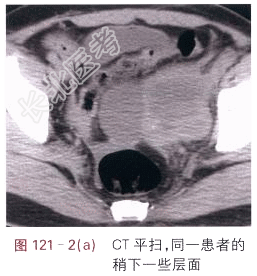

- [材料题] 患者,女,44岁,发现腹部包块2月余。体格检查:未见阳性体征。影像学资料如图121-1~图121-3所示。

- 简答题1、请叙述卵巢癌临床症状和该影像学表现?